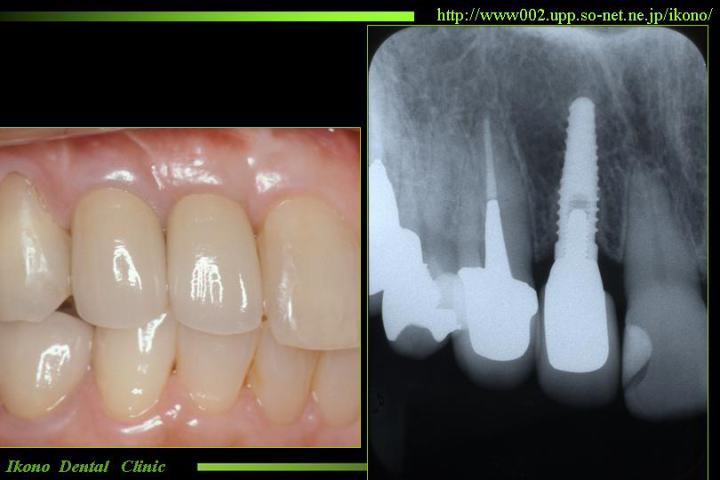

前歯のインプラント 前歯にインプラントを埋入しました。 前歯のインプラントを美しく仕上げるためにはインプラントの技術だけでなく、 再生療法など様々なテクニックが求められます。隣の歯を削らずに済みました。

上顎奥歯インプラント

当院での治療例(クリックで拡大)

上あごにインプラントを埋入するのに十分な骨がありませんでした。まずインプラントが埋入できる骨を造成してインプラントを植立しました。

インプラントを埋入だけでなく、歯周病の治療、噛み合わせの治療、といった病院の総合力が要求されます。